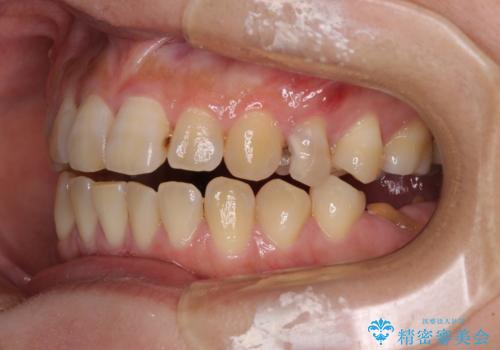

開咬により奥歯のみが接触している状態で、前歯部にほとんど接触のない状態で、奥歯に非常に負担のかかる咬み合わせでした。

治療の期間と費用はかかりますが、初診時とは比べものにならないほど良好な状態にて治療を終えることができました。